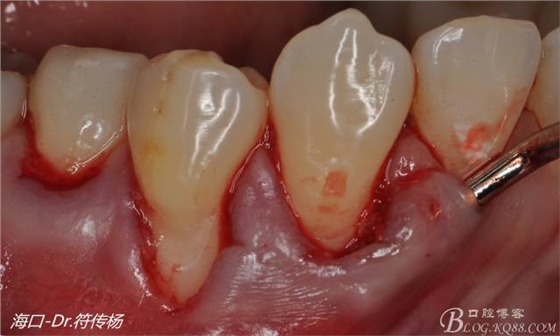

從病例圖片我們可以看到44牙頰側(cè)牙齦出現(xiàn)明顯萎縮

術(shù)前評(píng)估:退縮的齦緣在MGJ冠方 近遠(yuǎn)中牙槽嵴頂高度正常屬于Miller -Ι類牙齦退縮 所有術(shù)后可以完全覆蓋

首先用顯微手術(shù)刀切斷手術(shù)范圍內(nèi)的牙周韌帶

然后使用下頜開隧刀剝離牙齦

最后使用牙齦乳頭分離器分離牙齦乳頭